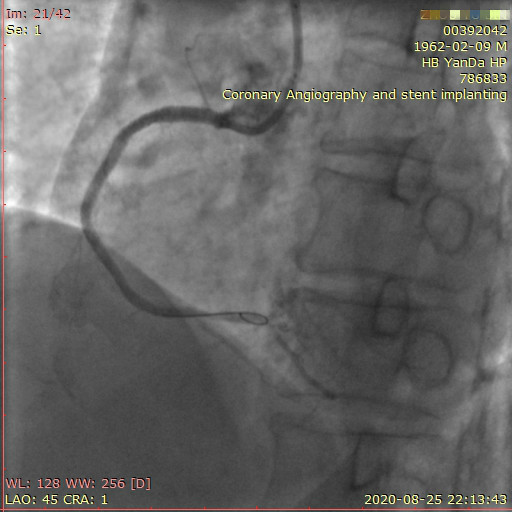

李先生右冠術前影像

李先生右冠術后影像